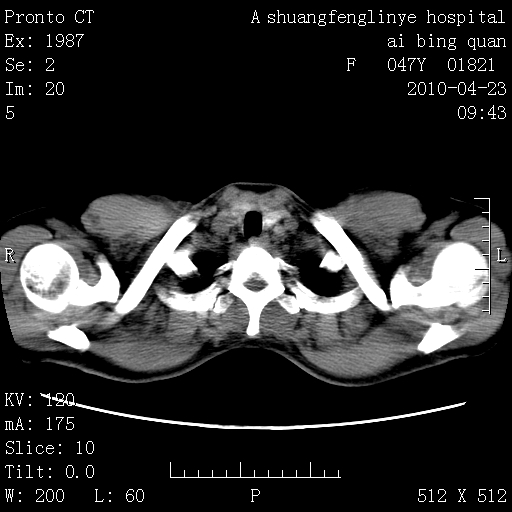

标题: CT25944:胸痛、气短、前几日高烧!肺Ca?请会诊! [打印本页]

标题: CT25944:胸痛、气短、前几日高烧!肺Ca?请会诊!

左侧乳腺低密度灶

双肺多发结节,部分密度较高,最大结节边缘光滑。临床有“胸痛、气短、前几日高烧”病史。首选考虑:右肺感染性病变!建议积极消炎后复查!